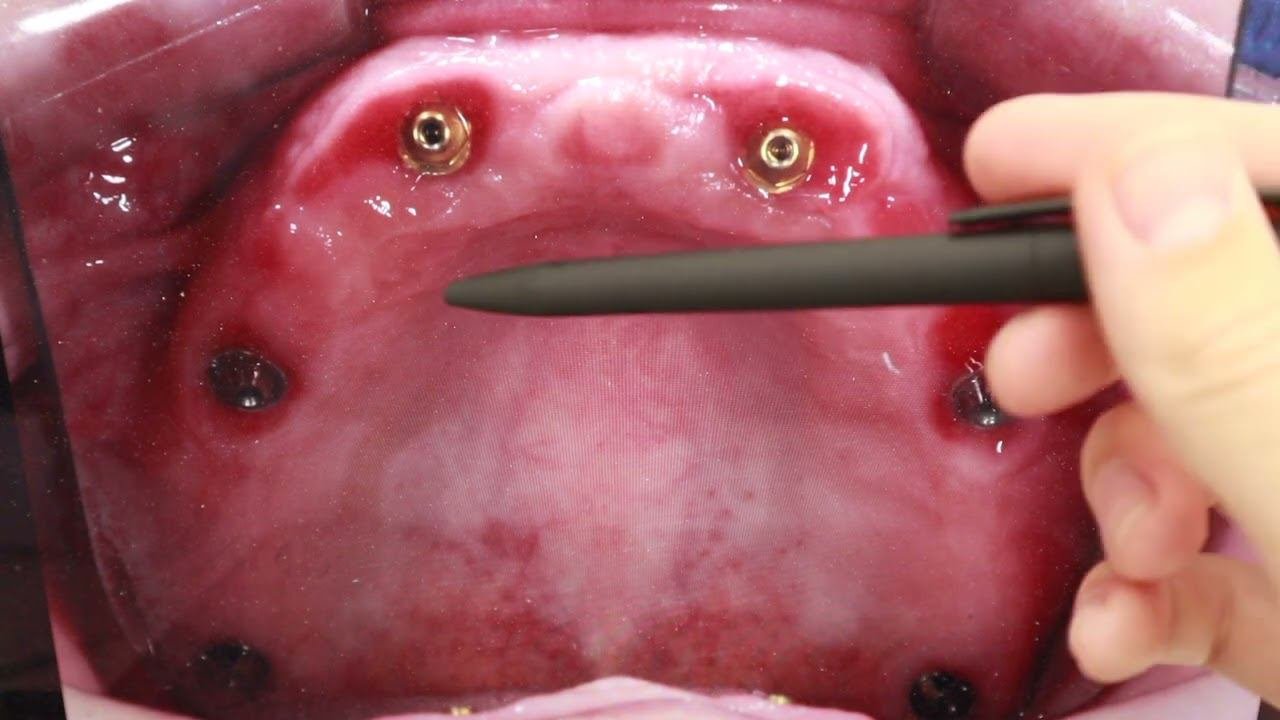

СТОМБУДНИ#18 ЧТО КУПИЛ НА ВЫСТАВКЕ_ #стоматология

Стомбудни#8.  ОТКУДА ДОСТАЛ ЗУБ_  ПЕРЕДЕЛЫВАЮ СВОЮ РАБОТУ

Стомбудни #6.  НИКОГДА ТАК НЕ ПРОТЕЗИРУЙ

СТОМБУДНИ#17  МАТЕРИАЛЫ! ЧЕМ РАБОТАЮ_ #стоматологическиематериалы